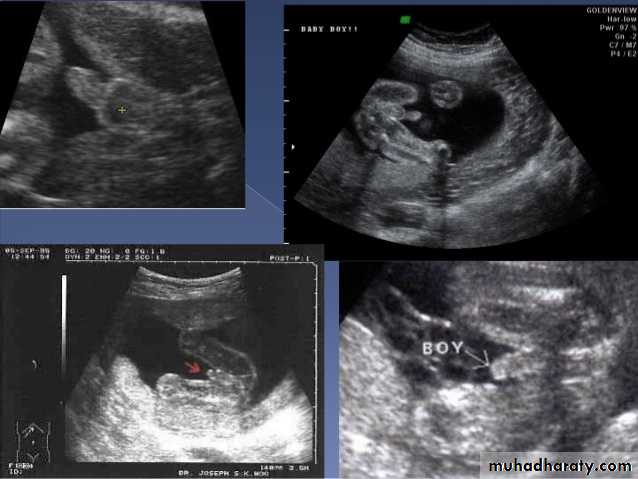

Male or female